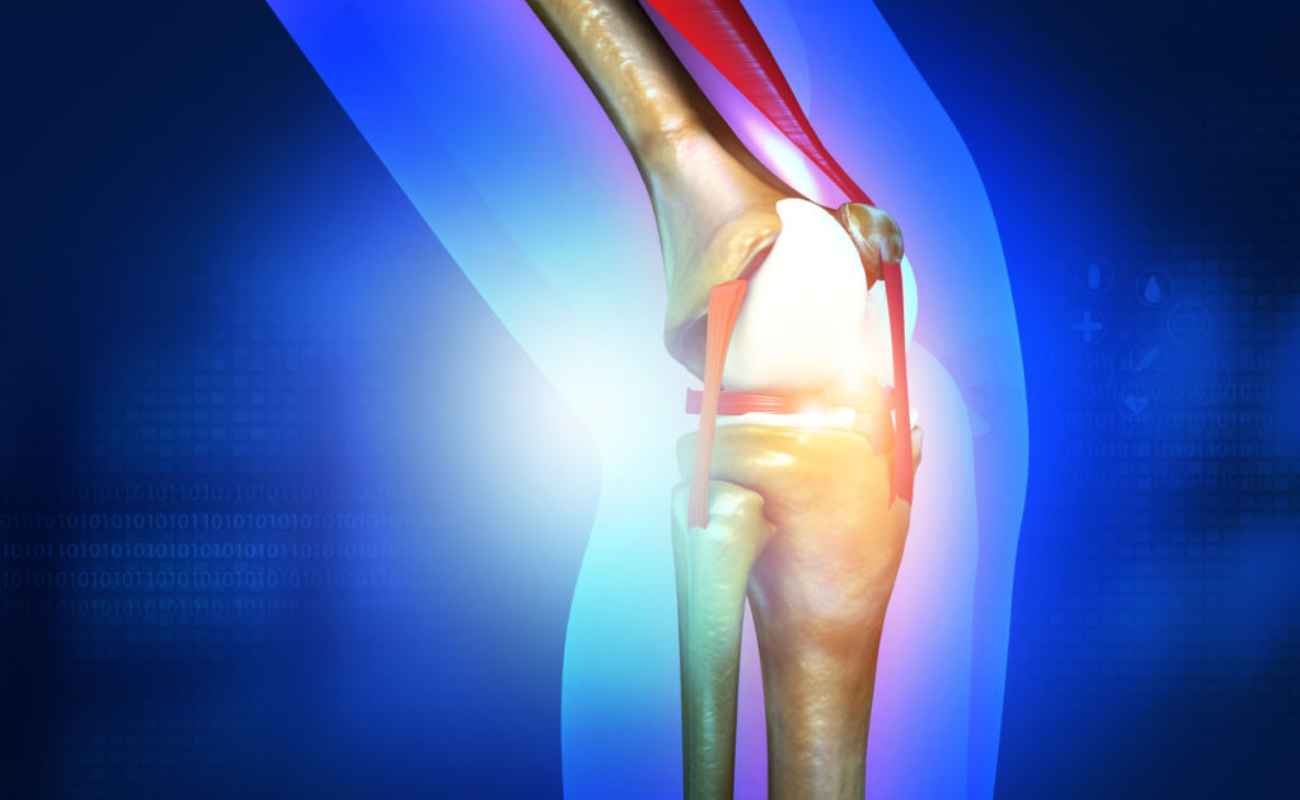

Ligament injuries

Ligaments are tough tissues that connect bones. The four main ligament in your knee are Anterior cruciate ligament (ACL), Posterior curciate ligament (PCL), Lateral collateral ligament (LCL) and Medial collateral ligament (MCL). Of these the ACL is injured the most.

ACL Reconstruction Surgery: What You Need to Know

The anterior cruciate ligament (ACL) is a crucial ligament that provides stability to the knee joint. However, ACL injuries are common, especially among athletes involved in sports that require quick direction changes or pivoting movements.

Understanding Meniscus Tears: Causes, Symptoms, and Treatment Options

The meniscus is a C-shaped piece of cartilage in the knee joint that acts as a cushion between the femur (thighbone) and tibia (shinbone). It plays a crucial role in absorbing shock, providing stability,

Preventing Sports-Related Knee Injuries: Tips and Techniques

Engaging in sports and physical activities offers numerous benefits for both the body and mind, promoting fitness, teamwork, and a healthy lifestyle.